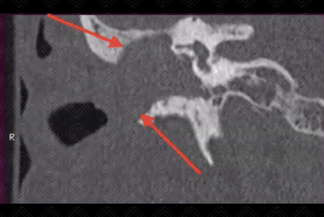

Texto alternativo para a imagem Créditos: Dra. Elazir Mota - Rio de Janeiro/RJ

Descrição da figura: Tomografia computadorizada da mastoide no plano coronal. Erosão das paredes do conduto por material de partes moles (colesteatoma - setas vemelhas).

• Tomografia computadorizada das mastoides : Excelente método de imagem quando há suspeita clínica, pela boa avaliação das estruturas ósseas, auxiliando no planejamento cirúrgico (reconstrução dos ossículos, quando necessário). O colesteatoma da pars flaccida origina-se do espaço de Prussak e usualmente, se estende posteriormente. Já o colesteatoma da pars tensa origina-se do mesotímpano;